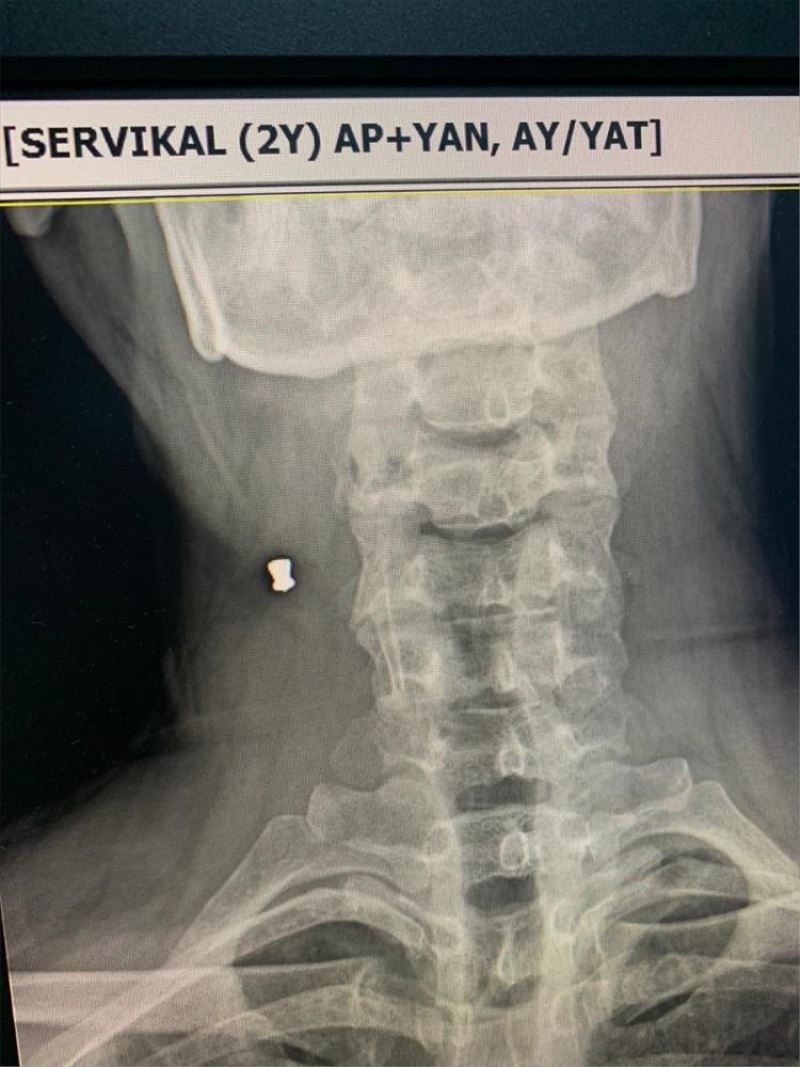

ISPARTA (AA) - YALÇIN ÇELEN - Isparta'da sandalyeden düsen Bilal Yilmaz, gittigi hastanede çekilen röntgen filminde 30 yildir boynundaki havali tüfek saçmasiyla yasadigini ögrendi.

Hastaneye giden Yilmaz'in, çekilen röntgen filminde boynunda havali tüfek saçmasi oldugu görüldü.

Yillardir boynunda bulunan saçmayi geçirdigi kaza sonucu tesadüfen ögrenmenin saskinligini yasadigini anlatan Yilmaz, "Röntgene girmeden önce görevliye üstümdeki metalleri çikarttigimi belirttim. Ancak boynumda metal oldugunu söyleyince ilk basta bir anlam veremedim. Sonra çocukken yasadigim olay aklima geldi. 10 yasindayken tarlada fare avladigimiz sirada bir arkadasimin tüfeginden çikan saçma bana isabet etmisti. Saçmanin boynuma girmedigini düsünmüstüm." diye konustu.

Saçmanin, sah damarina çok yakin bir bölgede durdugunu ögrendigini vurgulayan Yilmaz, "Basima bu kaza gelmemis olsaydi, saçmadan haberdar bile olmayacaktim. Bundan sonraki süreç farkli ilerleyecek. Farkli doktorlara gidecegim. Saçmayla yasamaya devam edecek miyim, bilmiyorum. Riskli bir bölgede. Doktor, '30 yildir orada duran bir seyi oynatmayalim' diyor." ifadelerini kullandi.

Süleyman Demirel Üniversitesi Tip Fakültesi Kalp Damar Cerrahisi Ana Bilim Dali Ögretim Üyesi Prof. Dr. Turan Yavuz da saçmanin atar damar ya da toplar damara isabet etmesi halinde müdahale edilmesi gerektigini söyledi.

Çikarilmasi için cerrahi bir müdahale yapilmasi gerektigini belirten Yavuz, "Bu saçma uzun yillar orada kaldigi için yapismistir. Bosuna cerrahi bir operasyon geçirmis olacak. Zarar vermez, böyle kalmasinda sakinca yok. Cerrahi bir operasyonda risk olusmaz." dedi.